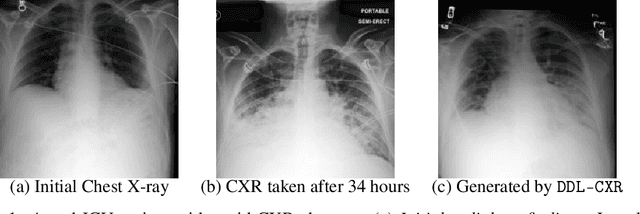

Abstract:Integrating multi-modal clinical data, such as electronic health records (EHR) and chest X-ray images (CXR), is particularly beneficial for clinical prediction tasks. However, in a temporal setting, multi-modal data are often inherently asynchronous. EHR can be continuously collected but CXR is generally taken with a much longer interval due to its high cost and radiation dose. When clinical prediction is needed, the last available CXR image might have been outdated, leading to suboptimal predictions. To address this challenge, we propose DDL-CXR, a method that dynamically generates an up-to-date latent representation of the individualized CXR images. Our approach leverages latent diffusion models for patient-specific generation strategically conditioned on a previous CXR image and EHR time series, providing information regarding anatomical structures and disease progressions, respectively. In this way, the interaction across modalities could be better captured by the latent CXR generation process, ultimately improving the prediction performance. Experiments using MIMIC datasets show that the proposed model could effectively address asynchronicity in multimodal fusion and consistently outperform existing methods.